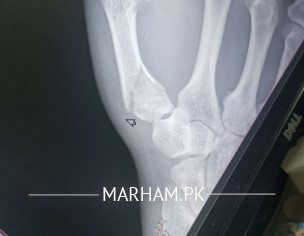

assalam u alaikum mera thumb 17 days pehle thoot gaya tha oer mene 15 days k leye plaster/cast lagaya leken mene ehtiat nahi ki per mene aj x ray leya to thumb ki halat wese ki wese hai. guide kare please kia karna chaheye

please apply pop again and keep it for 30 days.

Your thumb must be incorporated in the POP.

fracture is still not displaced.

it has acceptable position, However need to tailor the treatment plan according to patient need and dominance of hnad, profession etc nd I might fear you may have associated carple bone fracture.. scaphoid..?